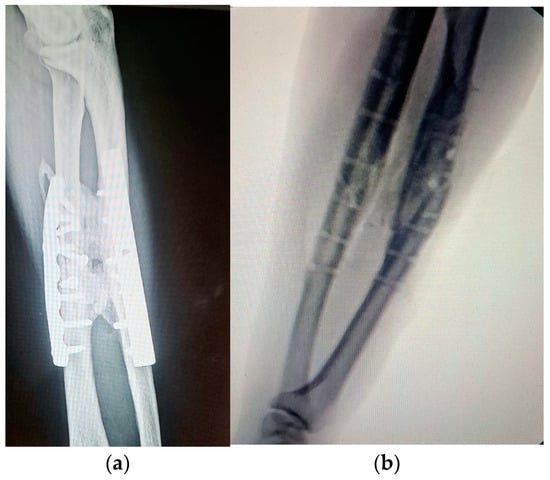

Bone fusion can occur anywhere along the forearm (from the wrist to the elbow) and is a rare complication of the traumatisms of the radius and ulna (Figure 1). Depending on the case series examined, the incidence is from 0 to 9,4% of forearm fractures [1,2,3,4]. Every traumatism of the interosseous membrane can lead, in some circumstances, to the formation of fibrous tissue or a bone bridge (from hardware such as screws, external fixators, or plates used in surgery) [5,6]. Because the radius has a normal movement of rotation over the ulna in pronation, the new bone bridge formation (synostosis) between these two bones blocks it. Extension of the bone proximal to elbow provokes stiffness of the joint.

Figure 1. Radio-ulnar synostosis after a car accident involving the elbow and forearm.